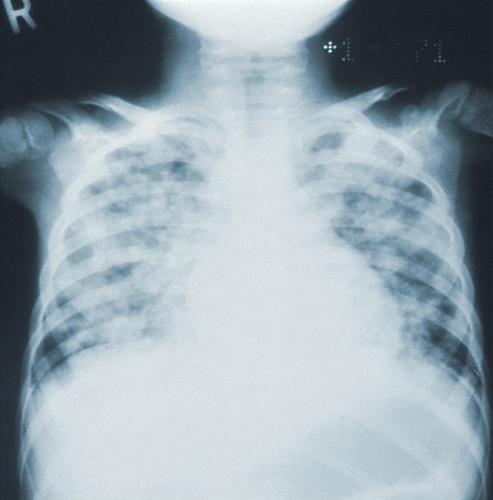

폐렴과 전염에 대한 요약 내용:폐렴은 호흡기 감염으로 인해 발생하는 흔한 질환입니다. 주로 세균, 바이러스 또는 균류에 의해 감염되지만 기타 원인으로도 발생할 수 있습니다. 폐렴은 폐에서 염증과 액체 축적으로 인해 호흡 과정에 심각한 영향을 줄 수 있습니다.

전염은 질병의 전파를 의미하며, 폐렴은 전염성 질병입니다. 주로 호흡기 분비물을 통해 사람에게 전파될 수 있습니다. 사람은 폐렴 환자와의 직접 접촉, 에어로졸 출혈, 비수면으로 인한 호흡기 분비물의 감염 등을 통해 폐렴에 감염될 수 있습니다.

따라서 폐렴과 만성 기관지염을 예방하고 조기에 치료하는 것이 중요합니다.폐렴은 주로 세균이나 바이러스 등 감염 요인에 의해 발생하며, 알레르기 반응, 방사선, 심각한 미세먼지 등에 의해 염증이 발생되어 발생할 수 있습니다. 다양한 원인이 있지만, 주로 감염으로 인한 경우가 많습니다.표에 내용을 정리하여 가독성 있게 작성할 수 있으며, 이를 위해태그를 사용해 표를 만들어 주세요. 텍스트는 폐렴과 전염에 관련된 내용으로 채워주세요. 폐렴 초기증상과 감기 전염 가능성에 대한 글을 마치며, 가족이나 지인 중 면역력이 약한 사람이 감기 증상을 보인다면 폐렴인지 주의 깊게 살펴보는 것이 중요합니다.